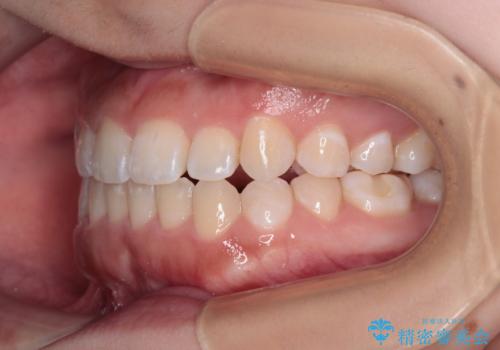

- 上下前歯のクロスバイトと叢生を気にして来院された患者様です。

インビザラインでの治療を希望されていて、デコボコの程度が中等度であり、安価なパッケージにて対応可能と判断されたため、インビザライン・モデレートを用いて矯正治療を行うこととしました。